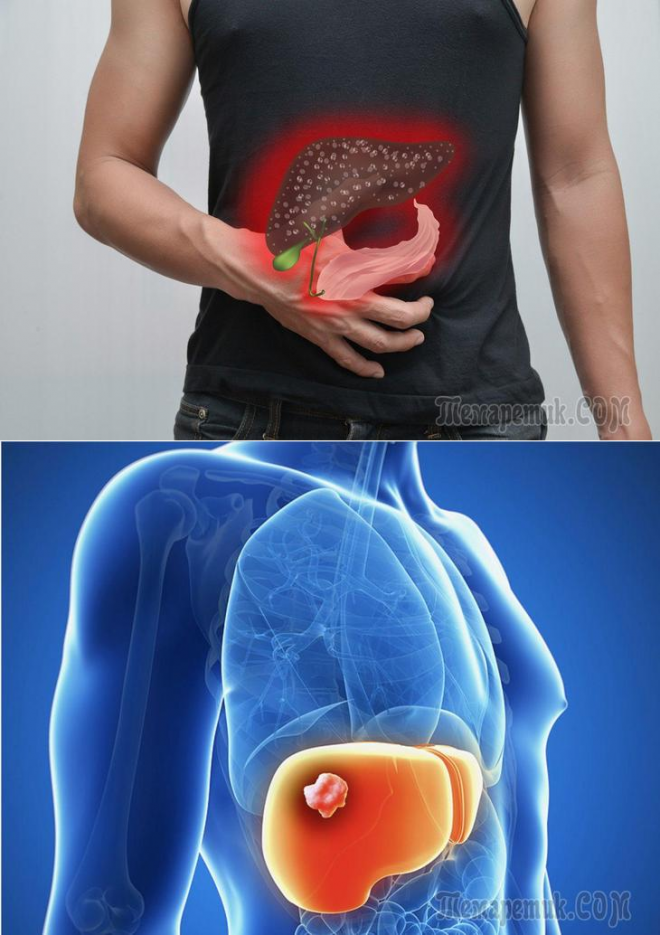

Признаки заболеваний печени: Важные симптомы и рекомендации